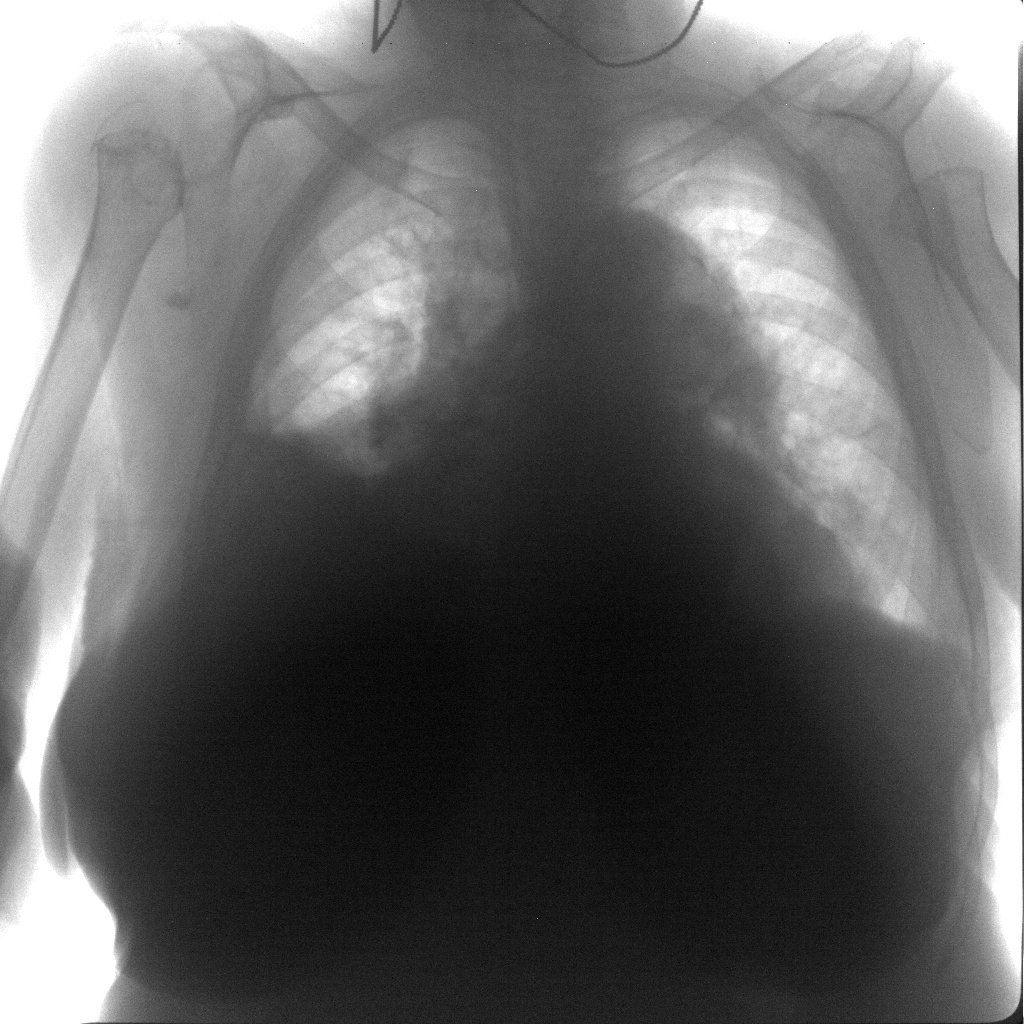

При осмотре отмечаются некоторое расширение и выбухание межреберных промежутков. Нарастающий объем жидкости оттесняет легкое кпереди и вверх, вследствие чего слой жидкости сзади становится более толстым, что при перкуссии очерчивает верхний край жидкости в виде линии Дамуазо, верхняя точка которой приходится на лопаточную линию. Над выпотом определяется тупой перкуторный звук. Важным клиническим симптомом наличия свободной жидкости является неподвижность нижнего легочного края. При значительных выпотах границы относительной сердечной тупости смещаются в здоровую сторону. Границу относительной сердечной тупости на стороне выпота можно установить с помощью метода аускультативной перкуссии. При аускультации над выпотом определяется ослабление или исчезновение дыхательных шумов, голосового дрожания и бронхофонии, однако при плевральных сращениях в зоне выпота эти симптомы могут отсутствовать. Непосредственно над выпотом может выслушиваться бронхиальное дыхание.

Важным признаком ПВ является смещение органов средостения. При парапневмонических плевритах средостение смещается в здоровую сторону. При выпоте, который сочетается с ателектазом или с пневмоциррозом, - в сторону поражения. Смещение органов средостения в сторону поражения при вторичном опухолевом плеврите при раке легкого является неблагоприятным прогностическим признаком.